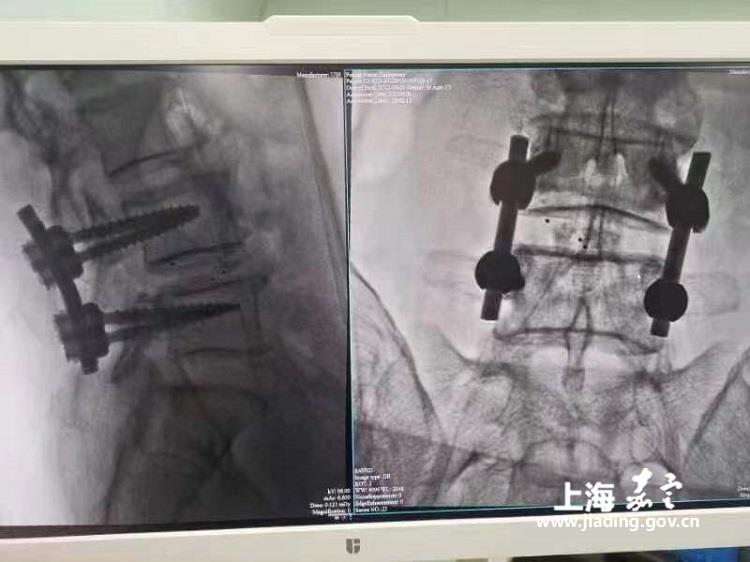

经紧急会诊,栾先生第一腰椎爆裂性骨折。CT证实患者骨折块侵入椎管内,对脊髓产生严重压迫,椎管容积被骨块占据,缩小到仅有原来容积的1/4。因此导致患者下肢的麻木感和痛觉越来越明显,大小便也很难控制。

“当时我们判断,需要立即对当事人进行急诊腰后路减压融合内固定术。"骨科副主任医师孙健介绍。腰后路减压融合内固定术的具有治疗比较彻底,疗效较好,而且维持的时间比较长,不容易复发等优点。

当天,腰后路减压融合内固定术仅耗时不到两小时,顺利完成椎管打开、骨折椎体复位。手术后,患者症状立即得到明显改善。术后第三天,栾先生双脚就活动自如,大小便恢复正常。

医院骨科脊柱团队经过对当事人身体的详细检查,诊断为腰椎椎管狭窄并L4/5椎间盘突出。经过慎重讨论后,决定采用腰后路减压融合内固定手术为老人解决病痛。

脊柱团队在完善相关检查、充分了解掌握老人整体状况下,为老人个性化定制了详细、缜密的手术方案。手术当日,仅用时一个多小时,为老人快、稳、准地完成了双侧充分减压和椎间融合、内固定手术。